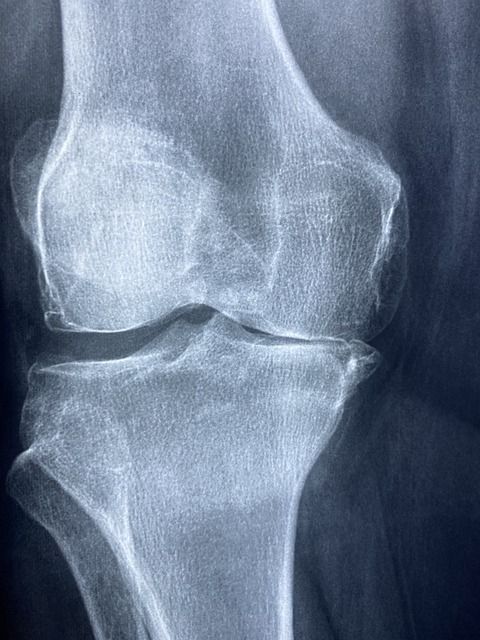

영상 검사

엑스레이와 초음파 검사도 진단에 유용합니다. 엑스레이는 관절의 손상 정도를 파악하는 데 도움을 주며, 초음파 검사는 요산 결정을 시각적으로 확인할 수 있도록 도와줍니다. 이러한 도구들을 통해 관절의 상태나 구조적인 이상을 확인할 수 있습니다.